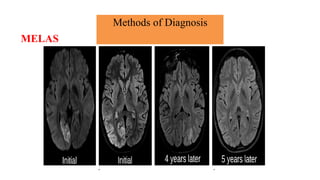

Brain magnetic resonance imaging

• Magnetic resonance imaging and spectroscopy are important tools in the diagnosis of

mitochondrial disorder.

• Brain atrophy is common in children with mitochondrial disease.

• Basal ganglia calcification are common in KSS and MELAS.

• Diffuse signal abnormalities of the white matter are characteristic of

KSS and myoneurogastrointestinal encephalopathy (MNGIE).

Methods of Diagnosis

Brain magnetic resonance imaging and spectroscopy

• The diagnosis of MELAS can be aided by the clinical association of stroke-like episodes with

radiological lesions that do not conform to the anatomical territories of blood vessels and

predominantly involve cortical gray matter.

• The initial or predominant lesions in MELAS are characteristically in the parietal- occipital

region.

• Leigh syndrome characteristically shows bilateral hyperintense signals on T2- weighted and

fluid-attenuated inversion recovery (FLAIR) MRIs in the putamen, globus pallidus and thalamus.

• MRS often detects lactate accumulation in the CSF and in specific areas of the

brain.

MELAS